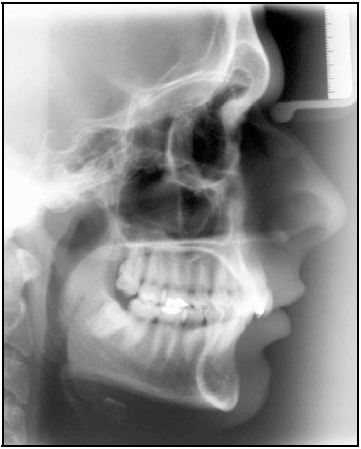

| grandezas | norma | paciente |

| SNA | 82º | 80º |

| SNB | 80º | 74º |

| ANB | 2º | 6º |

| WITS | -1 mm | +8 mm |

| SNGoGn | 32º | 24º |

| FMA | 25º | 22º |

| ENAENP.GoMe | 25º | 14º |

| 1.NA | 22º | 19º |

| 1-NA | 4 mm | 2 mm |

| 1.NB | 25º | 27º |

| 1-NB | 4 mm | 4 mm |

| Pog-NB | 2,5 mm | 3 mm |

| FMIA | 68º | 56º |

| IMPA | 87º | 107º |

| H.NB | 12º | 13º |

| H-Nariz | 9-11 mm | 6 mm |

| ângulo nasolabial | 110º | 127º |

| S-Go × 100% / N-Me | 62% a 65% | 71% |